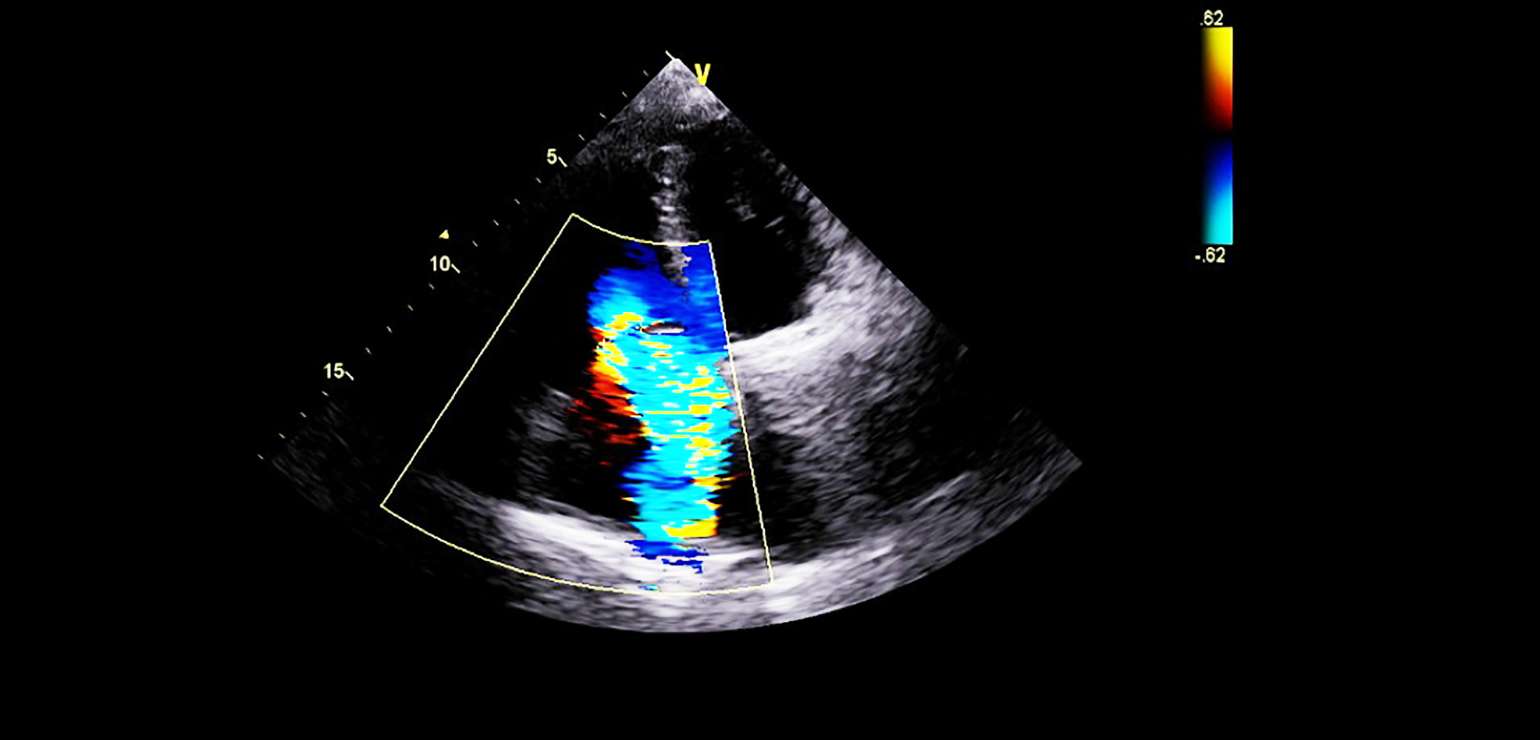

Color Doppler

What is a Color Doppler?

The Doppler Ultrasound machine has high-end transducers that capture your blood flow in color, allowing your doctor to quickly spot the aberrations in blood flow caused by tumors, issues in your blood vessels, infections or other harmful abnormalities.